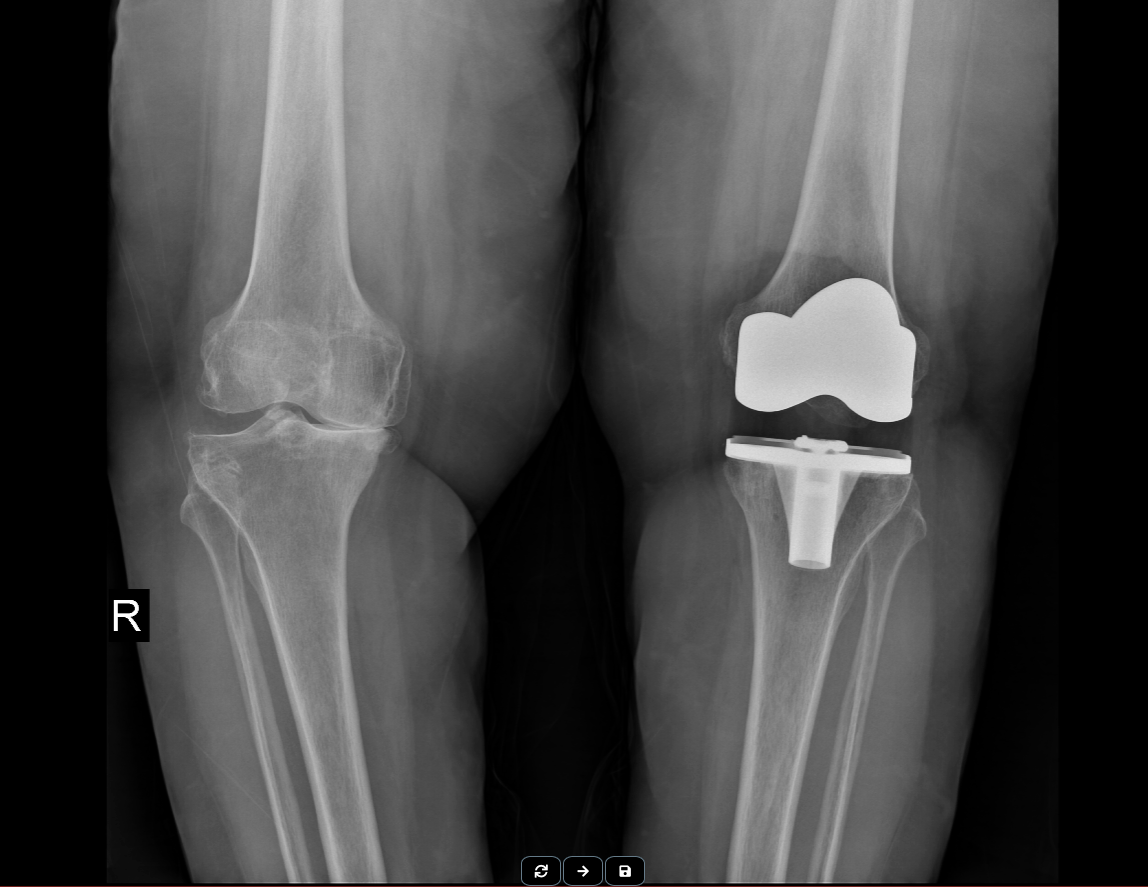

Total Diz Protezi

Total diz protezi, ya da diğer adıyla diz protezi, diz eklem kıkırdaklarında yaygın ve ciddi derecede bozulma olduğunda, yani diz ekleminde kireçlenme varlığında, ağrının giderilmesinde kullanılan en başarılı tedavi yöntemlerinden birisidir.

Bir total diz protezi uygulamasında kullanılan protezler temel olarak 3 bölümden oluşur. Bunlar femur adı verilen uyluk kemiğinin alt ucunu örten parça, tibia adı verilen kaval kemiğinin üst ucunu örten parça ve son olarak da bu iki kısım arasında hareketliliğe katkı veren; sürtünmeyi azaltan insört adı verilen kısım.

Bazı ameliyatlarda ise bu temel 3 parçanın haricinde ek olarak başka parçalar da gerekli olabilmektedir. Protezler ekleme yerleştirilirken duruma göre vida ya da kemik çimentosu gibi malzemeler kullanılmaktadir.